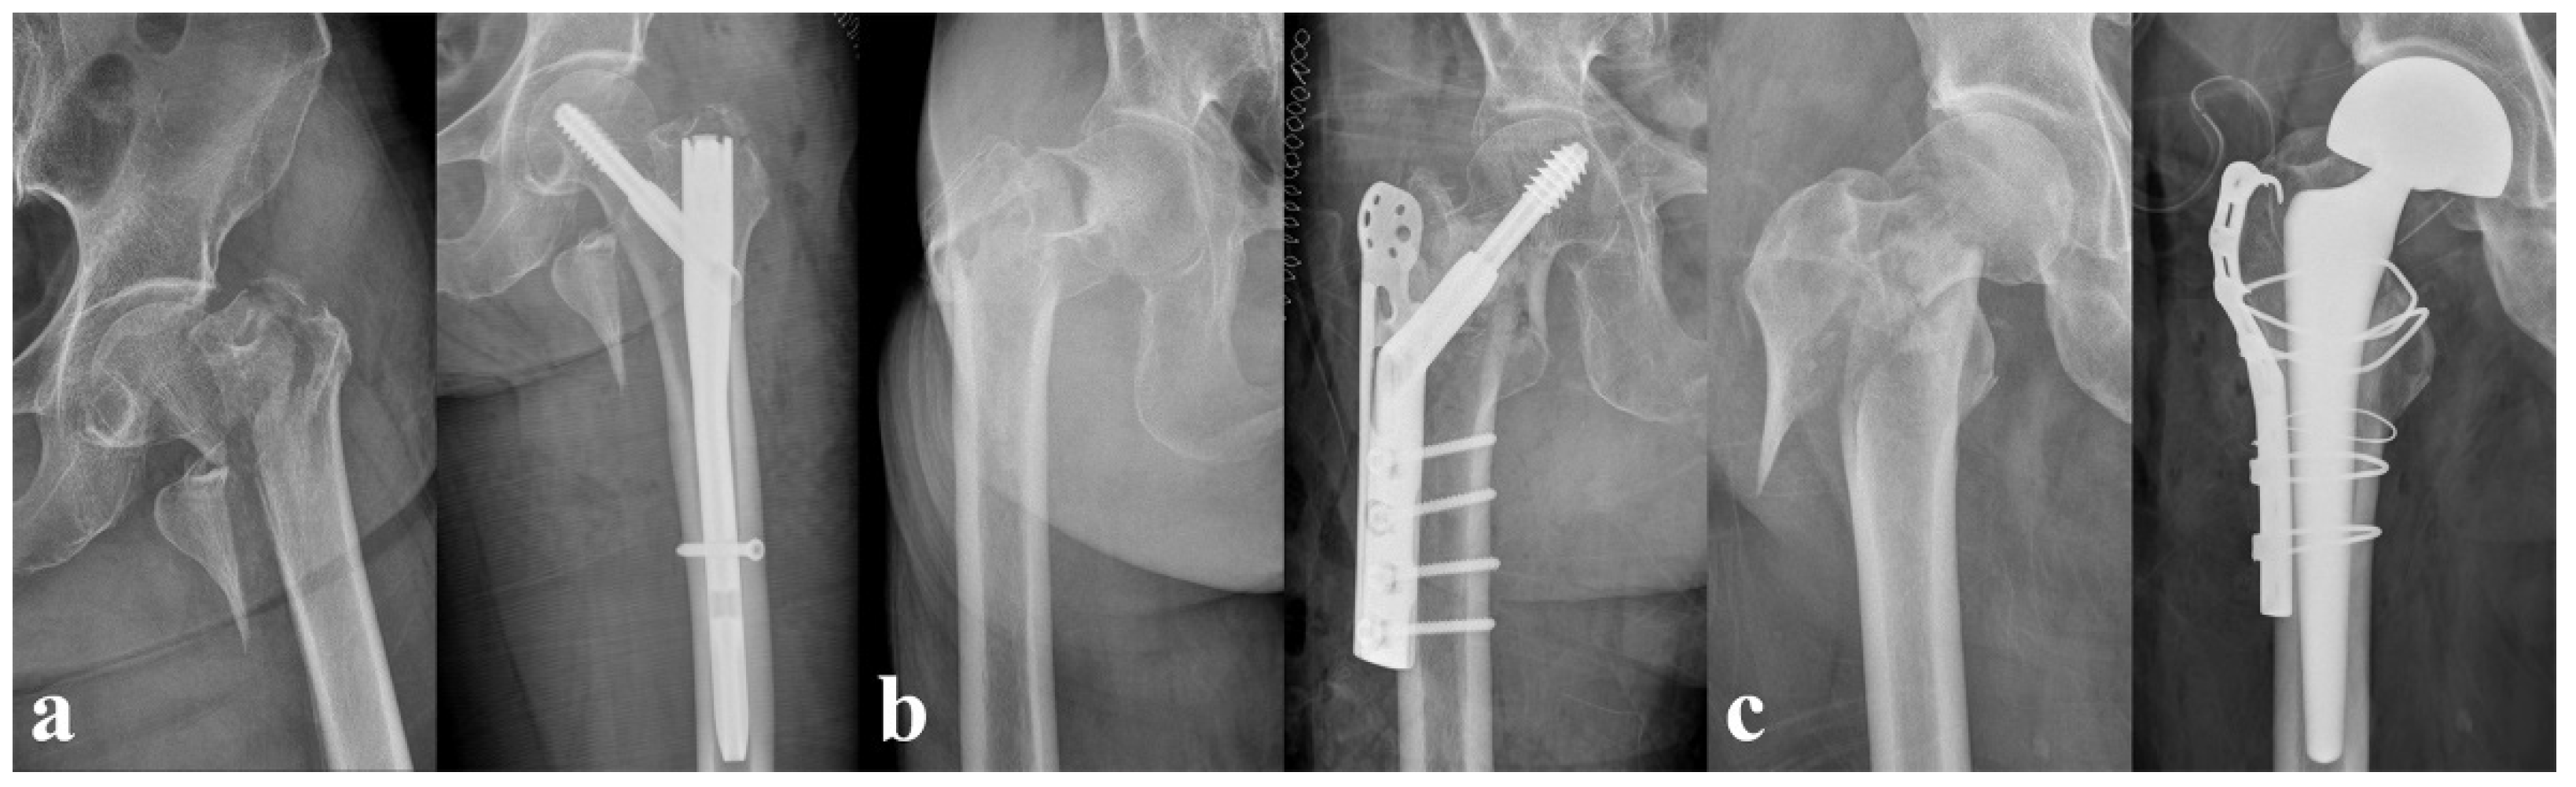

For the HR surgery, we performed a total hip arthroplasty using the Bencox® Cup System (Corentec, Seoul, Republic of Korea) with the Bencox® stem (Corentec, Seoul, Republic of Korea) for patients aged <70 years and bipolar hemiarthroplasty surgery using the C2 stem (Lima-LTO, Udine, Italy) or Bencox® stem (Corentec, Seoul, Republic of Korea) for the femoral component in patients aged >70 years. We applied trochanter reinforcement procedures with either a tension band wiring or trochanteric grip plate, only when an unstable abductor or trochanteric fragment was noticed intraoperatively. Figure 2 shows example cases of each treatment modality.

Figure 2.

Pre- and postoperative plain radiographs of different treatments. (a) A 72-year-old female who underwent cephalomedullary nailing. (b) An 88-year-old female who underwent dynamic hip screw fixation. (c) A 73-year-old male who underwent bipolar hemiarthroplasty.